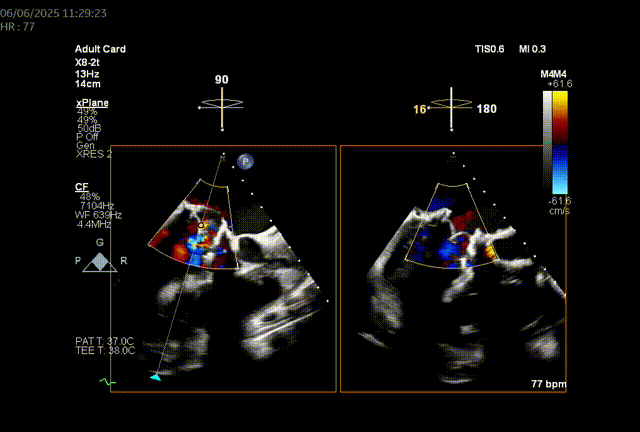

由于二尖瓣环和主动脉瓣角度过大,若采取经心尖方式,同轴性不佳,且难以调整定位件,同样采取经房间隔方式。

模拟植入26mm的S3瓣膜,评估LVOT阻塞风险:

1.二尖瓣环与主动脉环平面夹角= 128.3°>105°

2.瓣膜与室间隔最短距离= 6.7mm>6mm

3.最小Neo-LVOT面积= 260.4mm2>180mm2

综合评估后LVOT梗阻风险低。